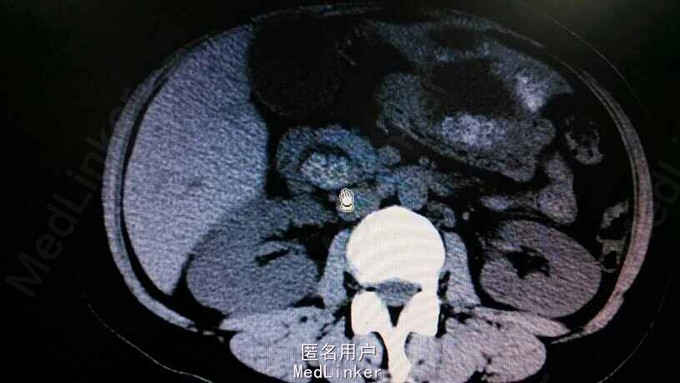

查体:右上腹轻压痛,无反跳痛,余无特殊。辅助检查,肝功,血象正常。腹部CT示肝内多发结石伴胆管囊状扩张。胆总管结石。见图

诊断:肝胆多发结石。治疗:予覆盖敏感菌,利胆等治疗。外科会诊:无法手术,内科治疗为主。